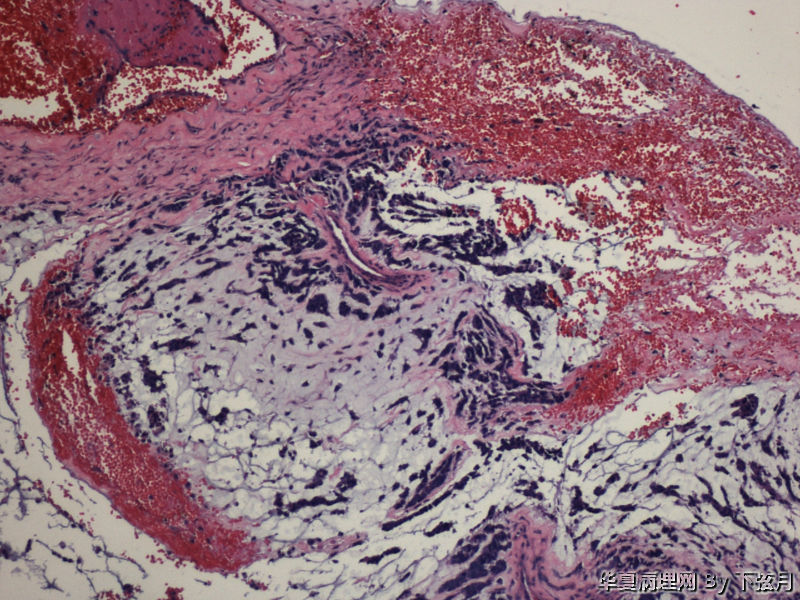

左侧颞叶及胼胝体膝部占位图1

名称:图1

描述:HE 40倍

从图1可见肿瘤似位于脑皮质外围,有粘液背景,部分如脊索瘤样,倾向于脊索瘤样脑膜瘤。